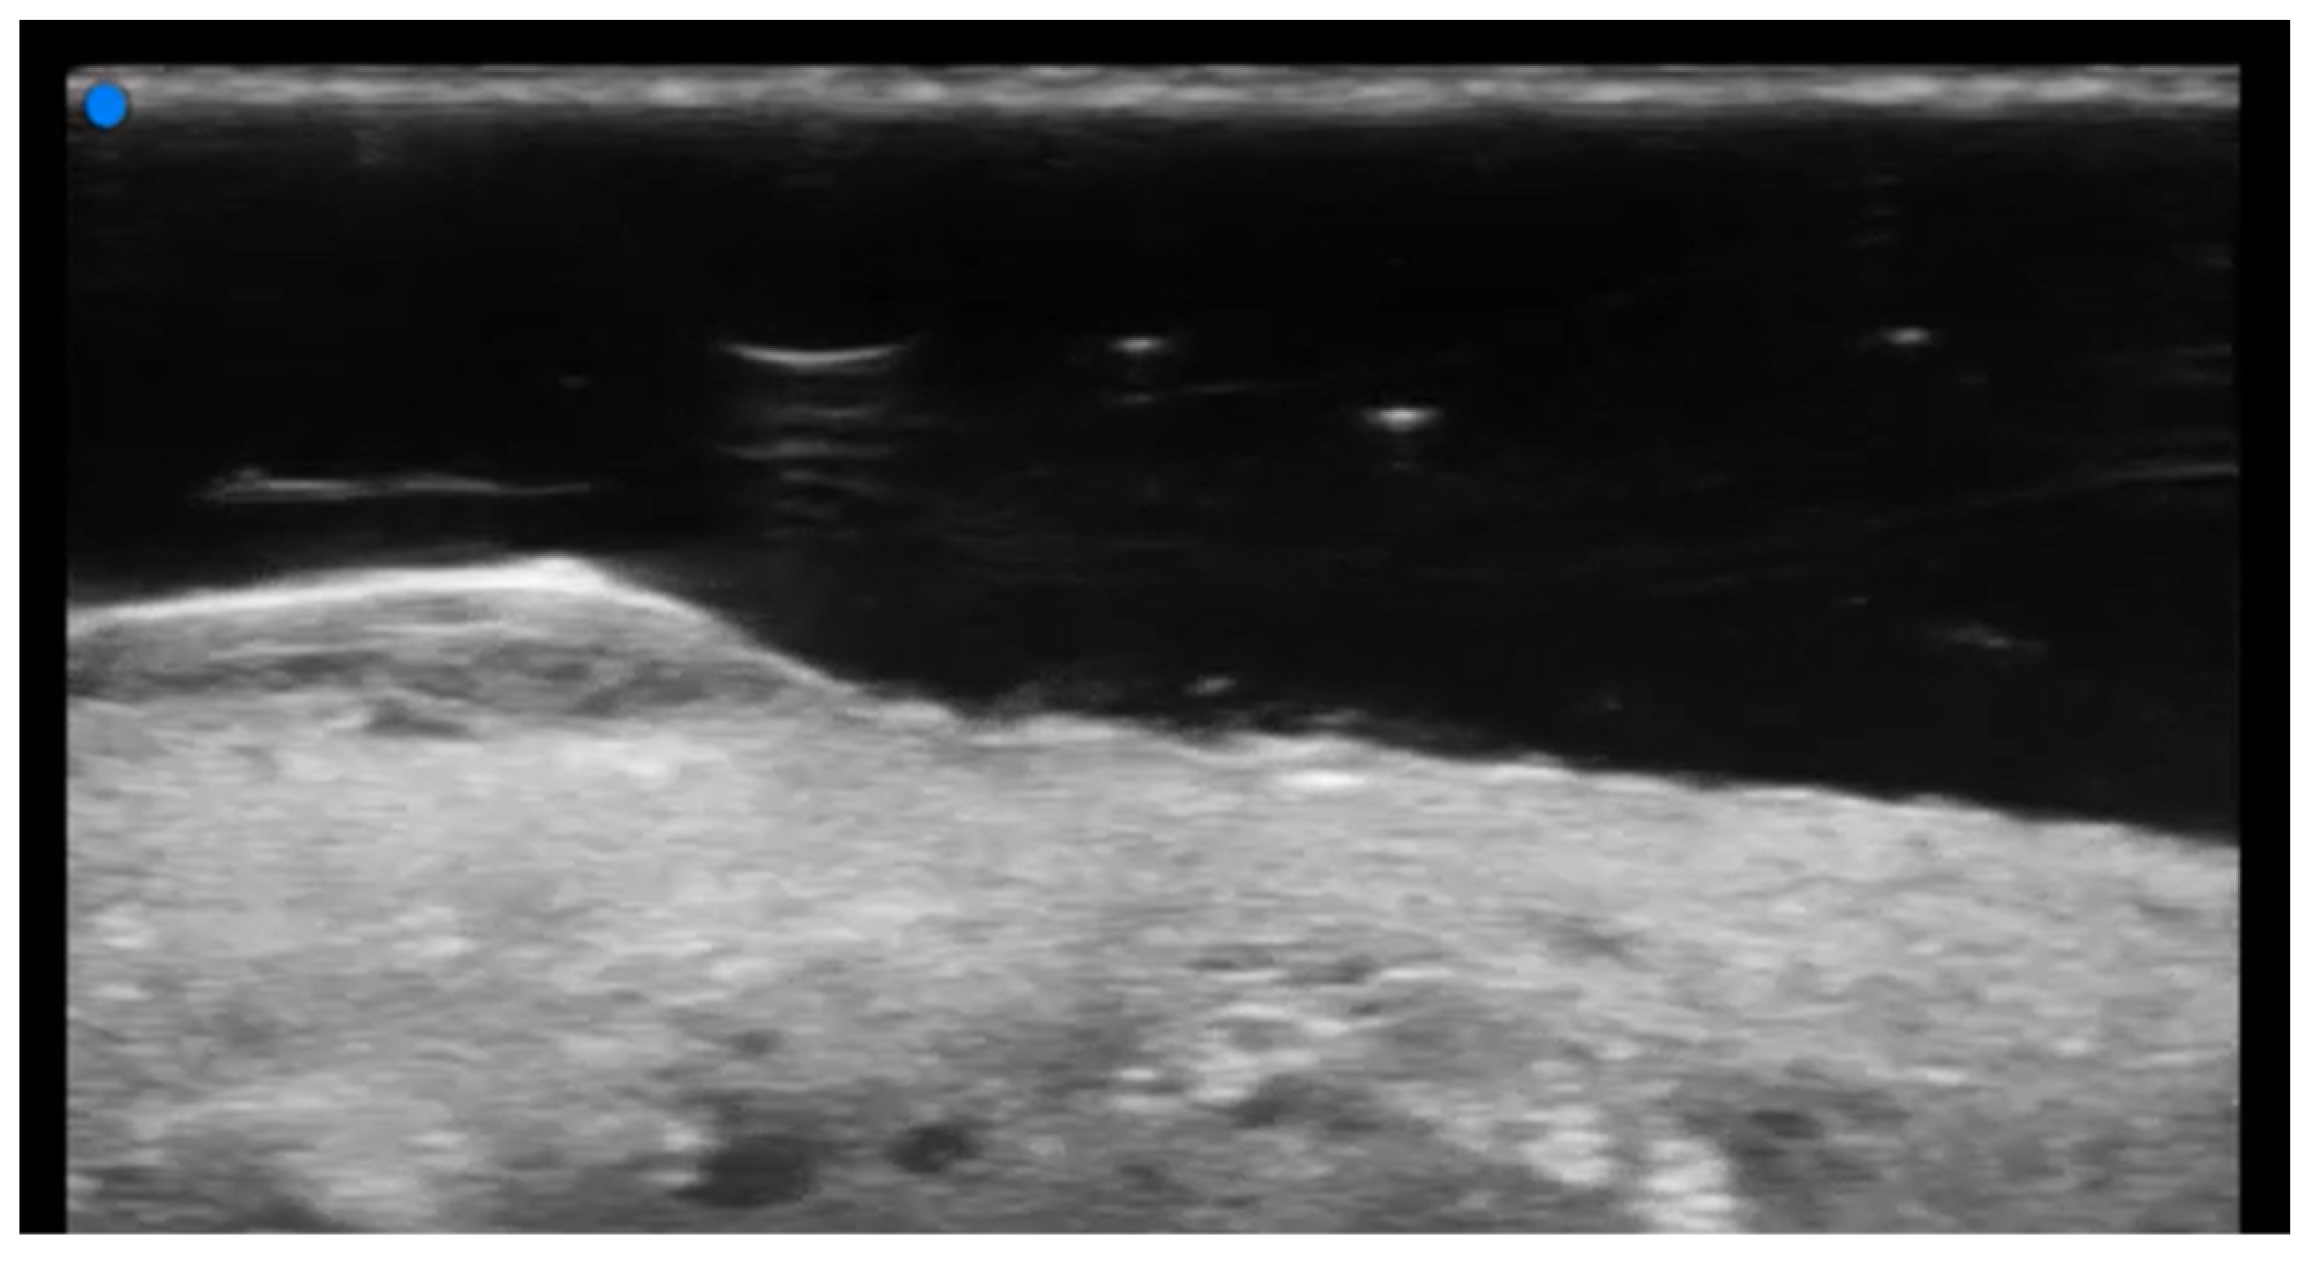

- Etesami, I.; Azizi, N.; Sabrinejad, R.; Montazeri, S.; Kamyab, K.; Nasimi, M.; Mahmoudi, H.; Khorasanizadeh, F.; Wortsman, X. Sonographic skin features and shear wave elastography in distinguishing active from inactive morphea lesions: A case-control study. J Am Acad Dermatol. 2025, 92, 155–157. [Google Scholar] [CrossRef] [PubMed]